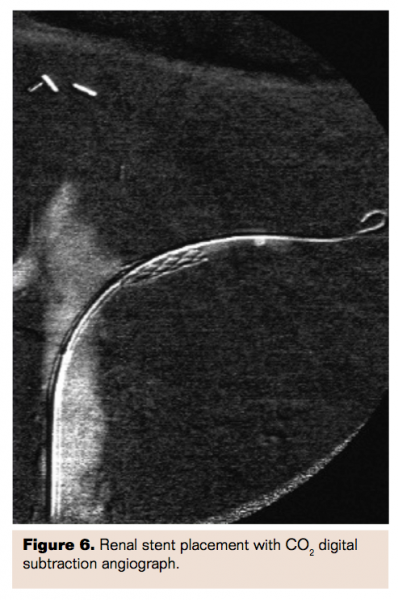

Given the pathophysiologic mechanisms of contrast nephropathy, there was interest in using intravenous fenoldopam, a dopamine-1 agonist and direct renal vasodilator, for prevention of contrast nephropathy. This approach quickly gained popularity but ultimately was proven to be of no benefit in the CONTRAST trial.8 The likely reason for failure was elucidated in work done by Tierstein et al9 which evaluated the effect of intravenous vs intrarenally (IR) delivered fenoldopam. Tierstein demonstrated that there was no increase in renal blood flow or glomerular filtration rate associated with the doses of intravenous fenoldopam utilized in CONTRAST and higher doses were not possible due to limitations of systemic hypotension. Conversely, IR fenoldopam delivered using a specialized bifurcated “Benephit” catheter (Figures 2, 3; AngioDynamics) significantly increased renal blood flow and GFR by 25% and allowed the delivery of much higher doses of fenoldopam, typically 0.4 mcg/kg/min compared to 0.05 mcg/kg/min to 0.1 mcg/kg/min delivered intravenously. The prophylactic administration of IR fenoldopam for prevention of CIN became known as “targeted renal therapy” (TRT).

Multicenter, nonrandomized data was collected in the Be-RITE Registry.10 A total of 501 patients were treated between May 2004 and August 2007 at 19 centers and 285 of those undergoing percutaneous procedures were evaluable for CIN incidence at 48 hours. Patients received 145±78 mL of contrast. Baseline mean Cr was 2.01±0.58 mg/dL and 96% of patients had a baseline Cr>1.5 or CrCl<60 mL/min with mean baseline CrCl of 37±12 mL/min.

Placing the Benephit catheter was fairly simple with 95% success rate and average time to bilateral renal artery cannulation of 2.0±1.6 minutes. Infusion times varied considerably at 199±212 minutes. Mean creatinine levels were unchanged at 48 hours (2.00±0.73, P=.56). The predicted incidence of contrast nephropathy in this high-risk group using the Mehran model was 28.0% whereas the observed incidence of CIN was only 8.1%, a relative risk reduction of 71% (P<.0001).